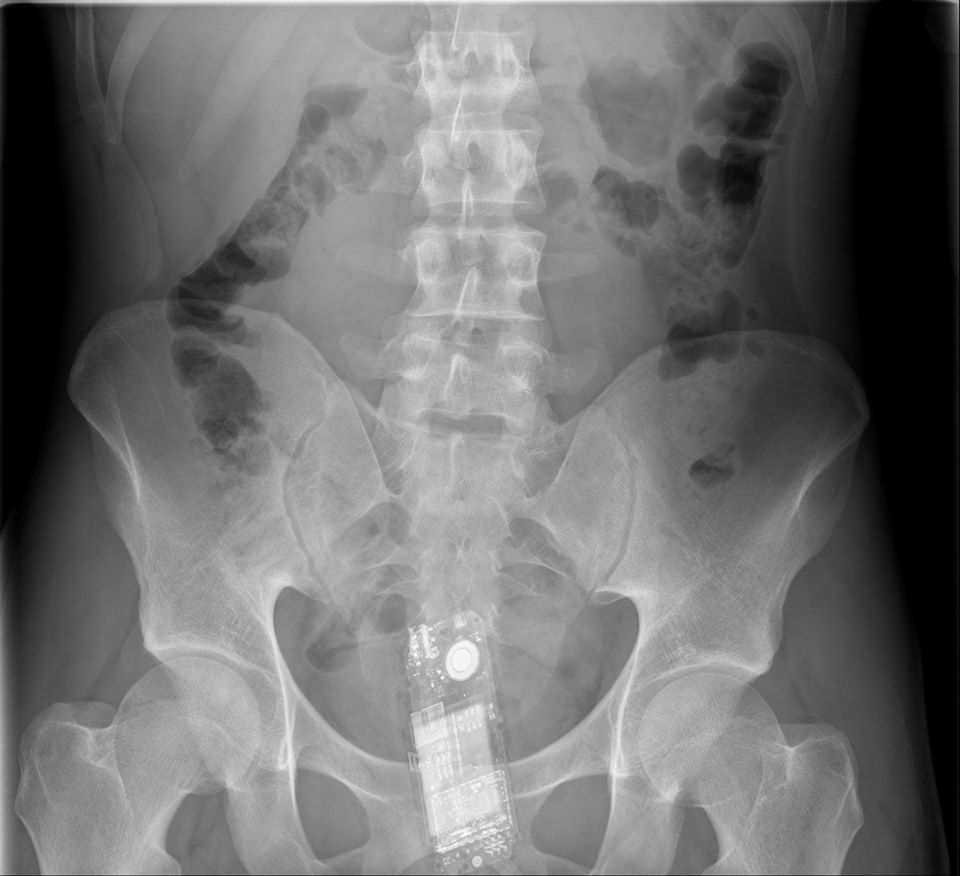

Celular:

Para começar a lista bizarra, que tal fazer um raio X e encontrar um celular ”perdido”? Bizarro né? Credo!!!